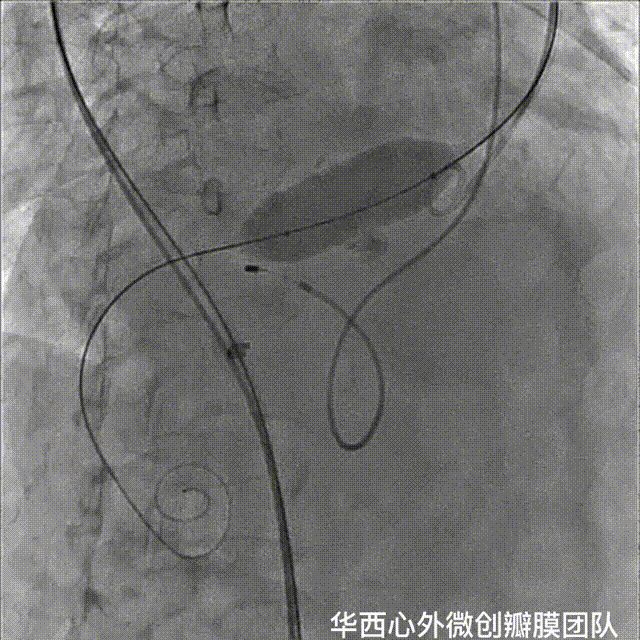

手术采用科凯生命科学自主研发的KoKaValve®经导管主动脉瓣膜系统,其瓣膜特点为短支架球囊扩张瓣膜设计,采用16F可扩张鞘管,从而适应更细的外周血管结构,此次手术采用23mm球囊扩张瓣膜,选择右侧股动脉为主入路,左侧股动脉为辅入路,颈内静脉植入临时起搏器,右侧股动脉植入16F可扩张鞘管,建立通路,跨瓣膜并置入Amplaz Super Stiff支撑导丝,采用配套20mm扩张球囊-2ml容量预扩张。

经过16F可扩张鞘输送23mm瓣膜至降主动脉,回撤瓣膜至输送器球囊部,采用可调弯输送系统过弓并精确定位于主动脉瓣膜。

在快心室率起搏下平稳释放瓣膜,瓣膜释放过程稳定,瓣膜准确铆定于主动脉瓣环。

停止起搏并撤回输送系统,撤出引导钢丝,关闭血管入路,术后瓣膜功能良好,无明显瓣周漏。